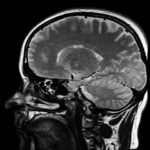

Группа исследователей предложила принципиально новый подход к терапии вируса папилломы человека, сообщает L24news. Речь идет о фотодинамической технологии, которая действует точечно — находит и ликвидирует только те участки ткани, где обосновался возбудитель.

Принцип работы выглядит так: человеку вводят фотосенсибилизатор — химическое соединение, которое избирательно скапливается в аномальных клетках. Затем на нужную зону направляют луч света определенной длины волны. Под действием излучения это вещество запускает каскад реакций, в результате которых образуются агрессивные формы кислорода. Они буквально выжигают инфицированные участки, при этом окружающие здоровые ткани остаются практически нетронутыми.

Главное отличие от вакцин — момент применения и цель. Прививки помогают предотвратить заражение, их делают до контакта с возбудителем. А фотодинамический способ нацелен на тех, кто уже столкнулся с инфекцией и носит ее в себе. Это терапевтический, а не профилактический инструмент. В эксперименте приняли участие женщины с подтвержденным диагнозом. После курса процедур у части испытуемых анализы перестали показывать присутствие вируса в организме, так как он просто исчез. Такой результат открывает перспективу для миллионов людей, у которых традиционные методы бессильны.